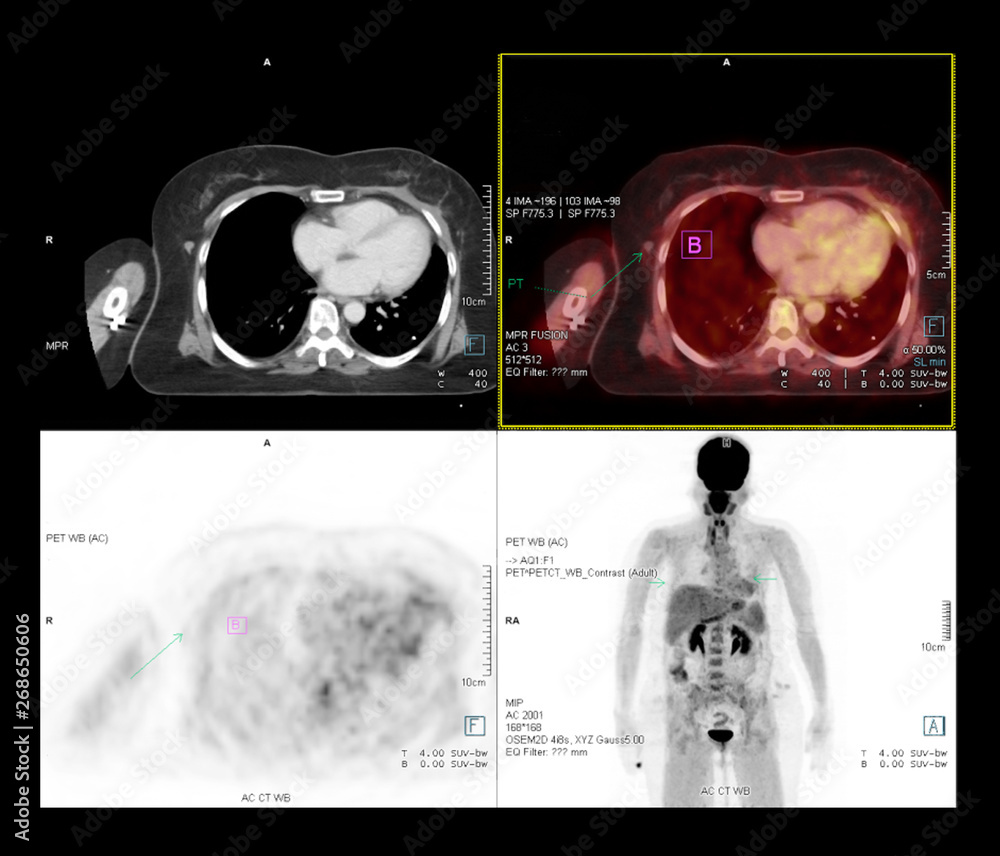

From stock.adobe.com

PET CT Scan image of whole body comparison Axial plane in CT scan and Is A Ct Scan Good For Detecting Cancer A ct scan can find certain types of cancer and can also: How does a ct scan help in detecting cancer? Ct scans provide an invaluable tool in the quest for accurate diagnosis. We consulted melissa chen, m.d., a neuroradiologist specializing in. Can a ct scan detect cancer? The benefits of a ct scan, especially if it is being. If. Is A Ct Scan Good For Detecting Cancer.